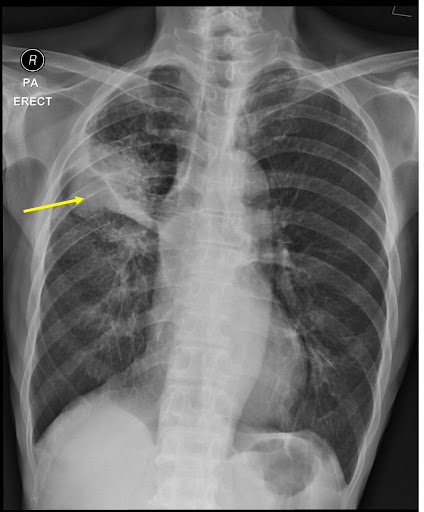

3. Location in the Lungs

- SCLC: Typically central (near the bronchi).

- NSCLC: Can be central (squamous) or peripheral (adenocarcinoma).